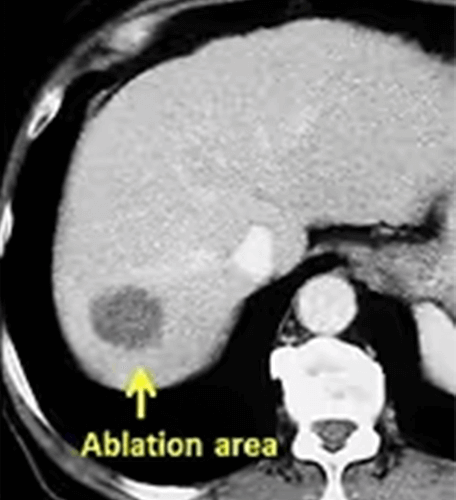

No matter what probe is used, as with all ablation methods, the purpose of RF ablation is to destroy the tumor and a normal tissue (safety margin) of 0.5-1cm thickness around it. If this can be accomplished, the tumor is completely ablated without the need for surgery. For a successful ablation, it is important to place the RF probe correctly in the tumor. Since a single probe is usually used in RF ablation, this probe should be in the center of the tumor. Otherwise, a part of the tumor can stay alive and grow again from this area (recurrence).

RF ablation is mostly used in liver tumors. It is the standard ablation method especially in hepatocellular carcinoma (HCC) and liver metastases.